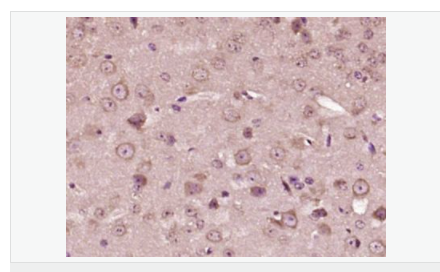

| 產(chǎn)品應(yīng)用 | ELISA=1:5000-10000 IHC-P=1:100-500 IHC-F=1:100-500 IF=1:200-800 (石蠟切片需做抗原修復(fù)) not yet tested in other applications. optimal dilutions/concentrations should be determined by the end user. |

| 產(chǎn)品介紹 | This gene encodes a member of the corticotropin-releasing factor family. The encoded preproprotein is proteolytically processed to generate the mature neuropeptide hormone. In response to stress, this hormone is secreted by the paraventricular nucleus (PVN) of the hypothalamus, binds to corticotropin releasing hormone receptors and stimulates the release of adrenocorticotropic hormone from the pituitary gland. Marked reduction in this protein has been observed in association with Alzheimer's disease. Autosomal recessive hypothalamic corticotropin deficiency has multiple and potentially fatal metabolic consequences including hypoglycemia and hepatitis. In addition to production in the hypothalamus, this protein is also synthesized in peripheral tissues, such as T lymphocytes, and is highly expressed in the placenta. In the placenta it is a marker that determines the length of gestation and the timing of parturition and delivery. A rapid increase in circulating levels of the hormone occurs at the onset of parturition, suggesting that, in addition to its metabolic functions, this protein may act as a trigger for parturition. [provided by RefSeq, Nov 2015] Function: This hormone from hypothalamus regulates the release of corticotropin from pituitary gland. Subunit: Interacts (via C-terminus) with CRFR1 (via N-terminal extracellular domain). Subcellular Location: Secreted. Similarity: Belongs to the sauvagine/corticotropin-releasing factor/urotensin I family. SWISS: P06850 Gene ID: 1392 Database links: Entrez Gene: 1392 Human Entrez Gene: 12918 Mouse Omim: 122560 Human SwissProt: P06850 Human SwissProt: Q8CIT0 Mouse Unigene: 75294 Human Unigene: 290689 Mouse Unigene: 10349 Rat Important Note: This product as supplied is intended for research use only, not for use in human, therapeutic or diagnostic applications. CRF陽性神經(jīng)元的胞體廣泛分布于下丘腦的室旁核、背縫核和藍(lán)斑核,這些區(qū)域也是去甲腎上腺素(NE)神經(jīng)元與5-羥色胺(5-HT)神經(jīng)元密集的區(qū)域。 CRF既具有神經(jīng)遞質(zhì)的性質(zhì)又具有神經(jīng)激素的性質(zhì)。CRF是聯(lián)系神經(jīng)系統(tǒng)與內(nèi)分泌系統(tǒng)的橋梁,在情感障礙疾患如焦慮和抑郁的發(fā)病中發(fā)揮重要作用. |